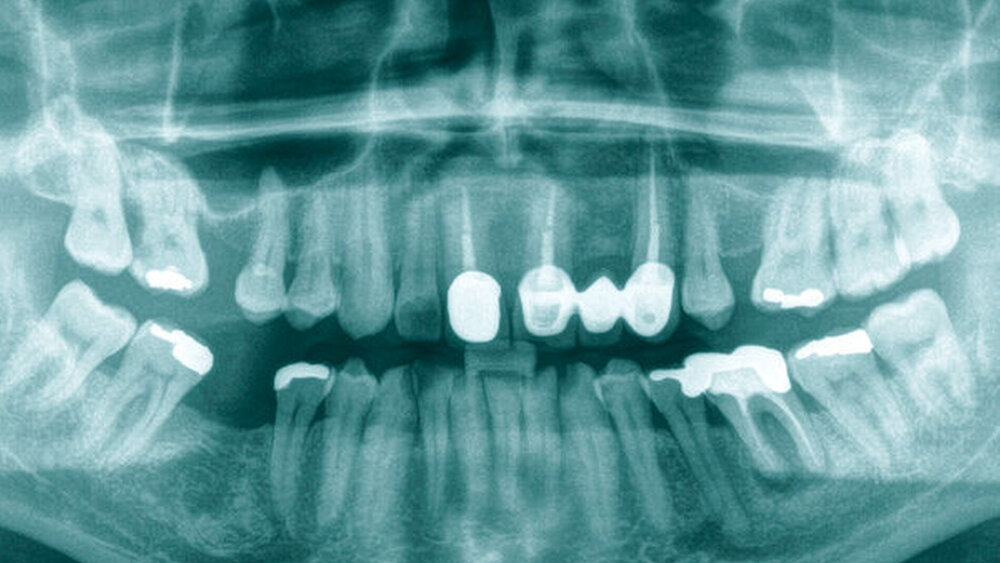

In der Panoramaschichtaufnahme (Abbildung 1) zeigte sich jedoch eine glatt begrenzte Aufhellung des rechten Capitulums. Zur weiteren Abklärung wurde eine Magnetresonanztomografie (MRT) des Gesichtsschädels veranlasst (Abbildung 2). Hier konnte eine Raumforderung im rechten Kiefergelenk nachgewiesen werden. Ergänzend wurde daraufhin eine CT-Untersuchung (Abbildung 3) durchgeführt, die einen im Durchmesser 31 mm großen Tumor mit Destruktion des rechten Capitulums zeigte.

Diese unspezifischen Symptome machen die Diagnose oft herausfordernd. Auch die zahnärztliche Bildgebung zeigt meist, wie in diesem Fall, nur unspezifische und keine wegweisenden Veränderungen. Die weiterführende Diagnostik sollte eine MRT und/oder CT umfassen. Hier zeigen sich häufig degenerative Veränderungen oder zystische Läsionen im angrenzenden Knochen, wobei aufgrund der Seltenheit der Erkrankung eine klassische bildmorphologische Charakteristik bisher nicht beschrieben wurde [Wang et al., 2019]. In der MRT, die als Goldstandard gilt, findet sich typischerweise sowohl in der T1- als auch in der T2-Wichtung eine niedrige Signalintensität. Folglich ist es radiologisch schwierig, einen TSRZT von anderen Riesenzelltumoren abzugrenzen, zumal manche Autoren den TSRZT als Tumorentität innerhalb eines Spektrums verschiedener Erkrankungen sehen [Wang et al., 2019].